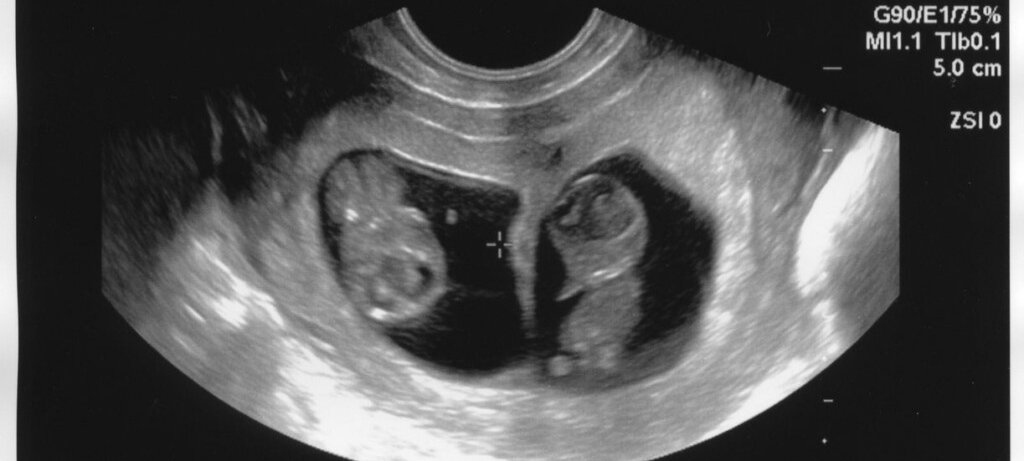

Чуть больше 1.5 года назад я была молодой мамой двойни, которую заботили простые материнские вопросы.

Конечно мое материнство началось внезапно, но чувствовала я себя вполне счастливо, не боясь трудностей.